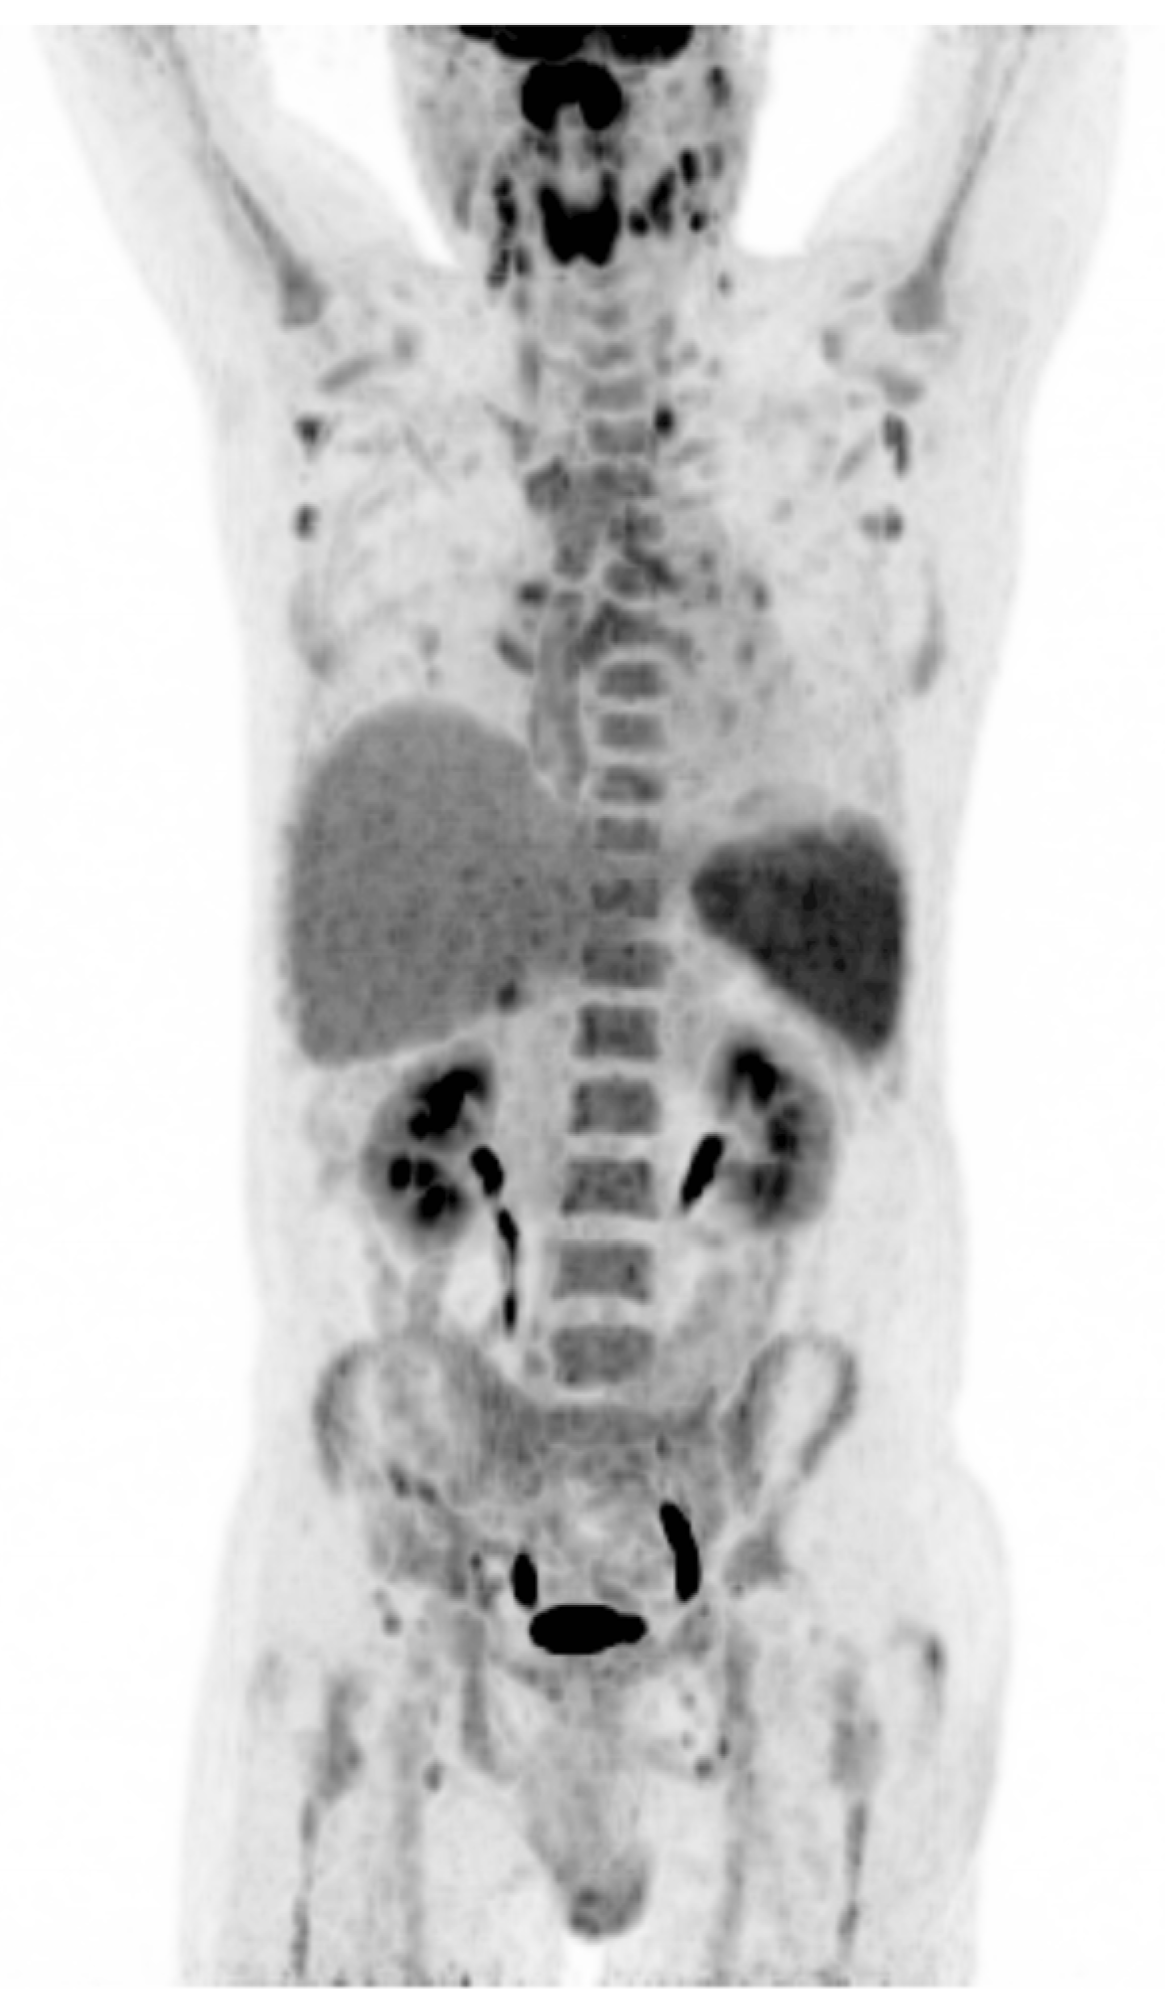

Due to persistent fever of unknown origin, a 18F-FDG PET/CT scan was performed. This showed intensely metabolically active, enlarged supra- and infradiaphragmatic lymph nodes including intensely increased metabolism of the lymphatic tissue of the Waldeyer’s pharyngeal ring, a splenomegaly with diffusely increased metabolism, and evenly increased metabolism of the bone marrow. No further metabolically active malignant foci were delineated (Figure 2).

Despite repeated negative EBV serology, the clinical picture—fever, lymphadenopathy, lymphocytosis with large unstained cells (LUCs), splenomegaly, and mild hepatitis—was suggestive of IM. EBV PCR therefore was performed and returned positive, confirming primary EBV infection as cause of the symptoms. Simultaneously, the results of the FDG PET-CT scan were obtained, matching the findings in this context as reactive due to the EBV infection and not as evidence of a malignant disease, such as a lymphoma.

Figure 2. 18F-FDG PET/CT scan (coronal maximum intensity projection) was ordered to evaluate fever of unknown origin. Intense uptake in the lymphatic tissue of the Waldeyer’s pharyngeal ring, the spleen, peripheral lymph nodes, and bone marrow are depicted consistent with a diagnosis of primary EBV infection in context of characteristic laboratory findings and not lymphoma. 18F-FDG = 18-fludeoxygluose; PET/CT = positron emission tomography/computed tomography.